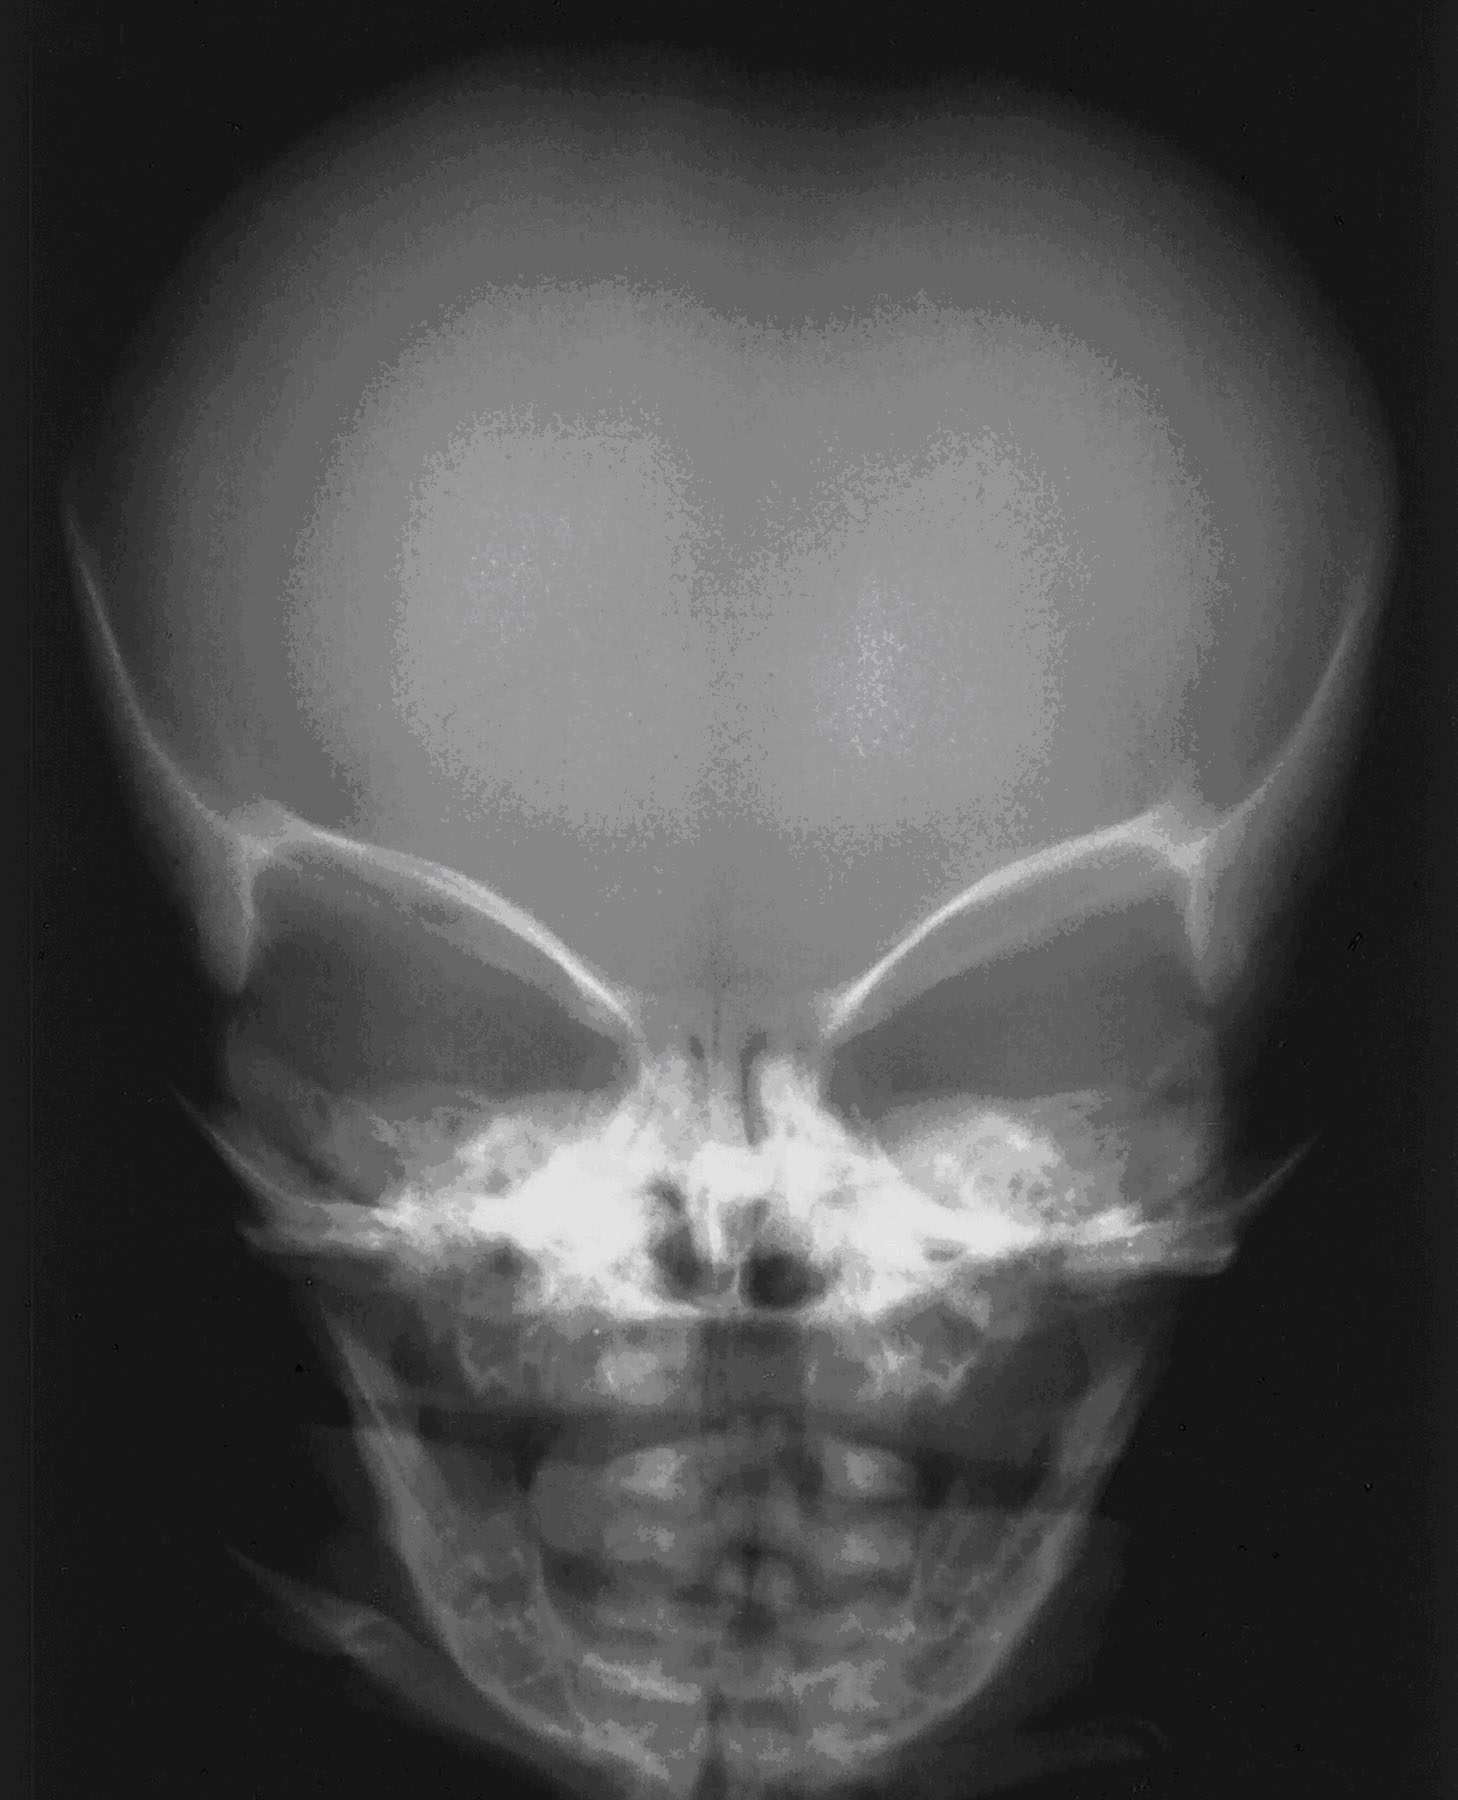

- An enlarged head (macrocephaly) with a prominent forehead.

Examination of the infant after birth shows increased front-to-back head size. There may be signs of hydrocephalus (“water on the brain”).

X-rays of the long bones can reveal achondroplasia in the newborn.